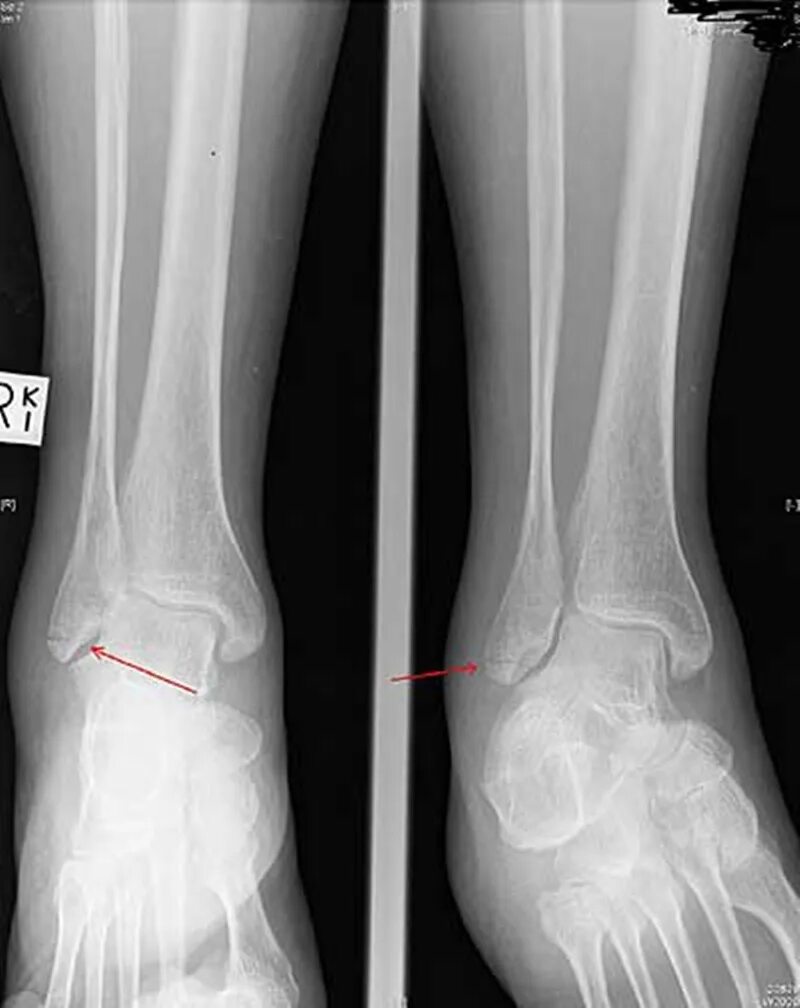

Перелом 3 берцовой кости